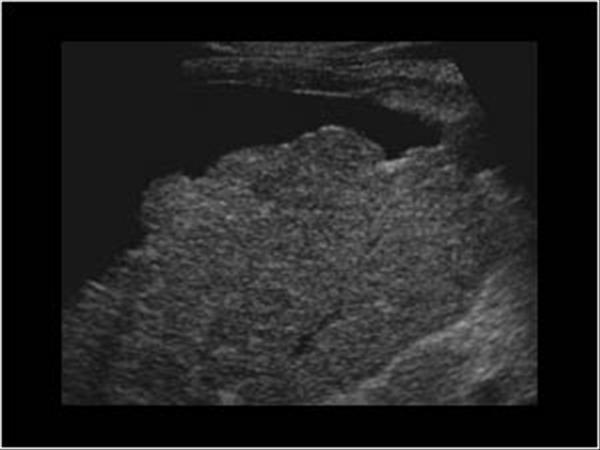

Portal Hypertension

Portal Hypertension

Budd-Chiari

Life threatening emergency

Portal vein Thrombosis - cavernous transformation

replacement of the normal single channel portal vein with numerous tortuous venous channels.